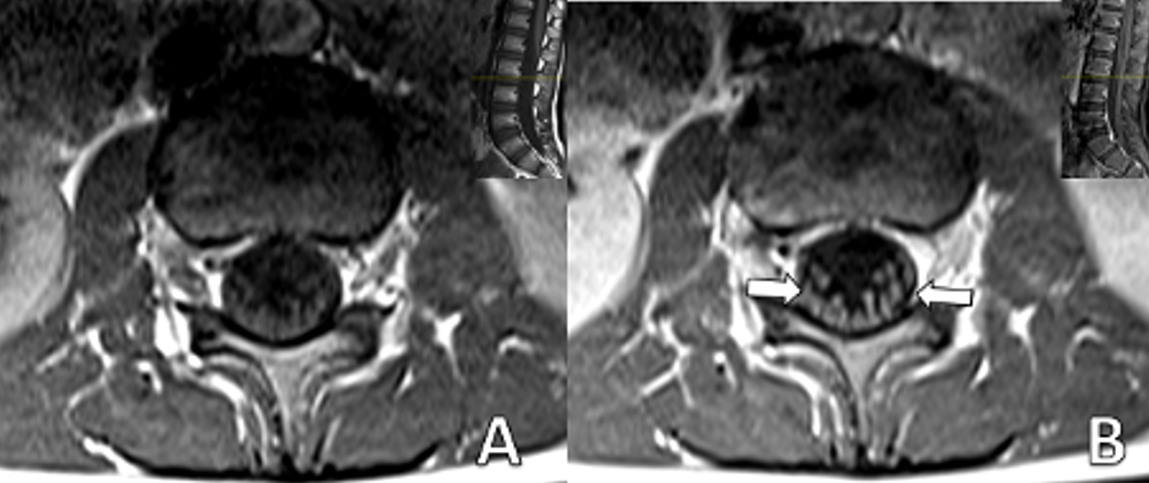

A 6-year-5-month-old male patient with no history of chronic illness presented with difficulty speaking, dyspnea, dysphagia, gait disturbance, and lower limb weakness in January 2022. He was referred to our center with those symptoms on the same day. Five days earlier, he had visited a local hospital for severe abdominal pain, nausea, and vomiting, diagnosed as acute gastroenteritis. On admission to our hospital, his vital signs were within normal limits. Neurological examination revealed no cranial nerve involvement, reduced muscle strength on both upper and lower extremities with a MRC scale of 3/5, and absent reflexes. No pathological reflexes were found. Abdominal and cremasteric superficial reflexes were intact and no sensory level was detected. Cerebellar function was assessed to be normal within the limits of the examination. CSF analysis showed an elevated level of protein (117 mg/dL). Spinal MRI showed significant contrast enhancement and thickening of the nerve roots of the cauda equina (Fig. 1 and Fig. 2).

Brain MRI: Millimeter-sized nonspecific white matter lesions. Spinal MRI: Axial T1 weighted fat-saturated image with contrast shows thickened enhancing roots of cauda equina |

All patients in this case series underwent brain and spinal MRIs. Radiological studies are essential to rule out other potential causes when nerve conduction studies and CSF examinations yield inconclusive results. An MRI of the spine is particularly helpful, as it can help exclude other conditions, such as transverse myelitis and compressive causes of polyradiculopathy. If a non-contrast MRI is performed, it is important to administer contrast media if a specific diagnosis is suspected, as the non-contrast sequences are usually normal.8 The most common site of enhancement in GBS is the anterior nerve roots, though enhancement of the posterior nerve roots can also occur.